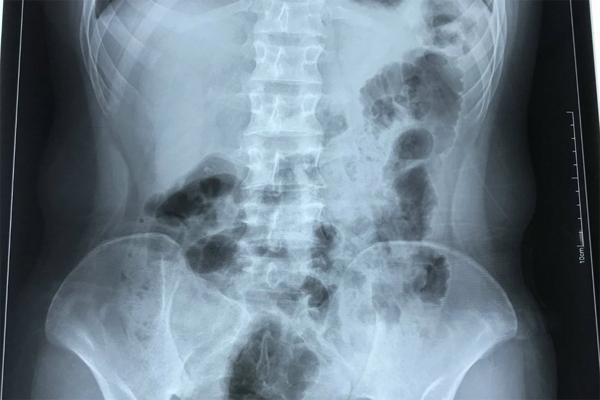

Kết quả siêu âm, chụp Xquang, bác sĩ chẩn đoán bệnh nhân viêm ruột thừa. Đặc biệt, phủ tạng chàng trai 17 tuổi đảo ngược, tim nằm bên phải.

Bệnh nhân H có trái tim nằm bên phải, vị trí nội tạng đảo ngược so với người bình thường.